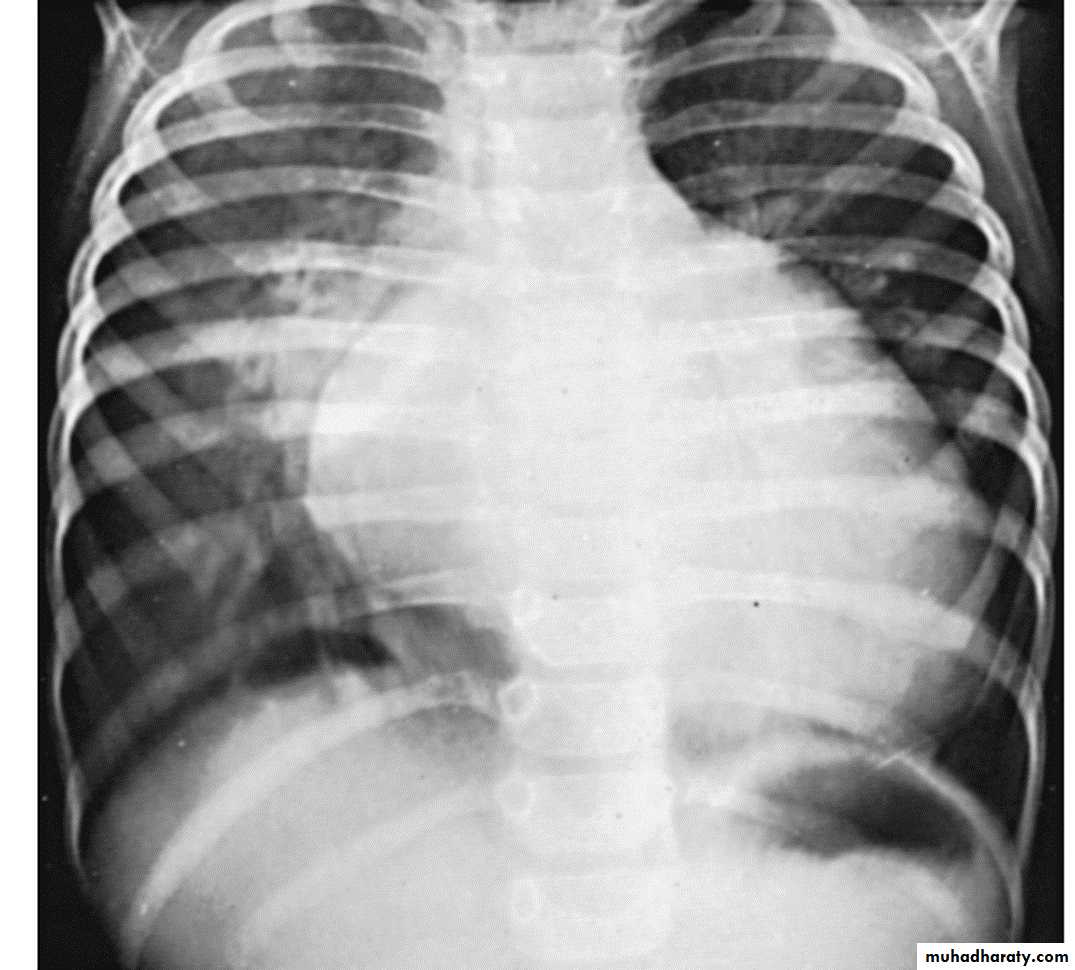

1- Chest-X ray show cardiac enlargement. Pulmonary vascularity is variable and depends on the cause of the heart failure. The cardiothoracic ratio (C/T ratio) is higher than the normal for age.

Normal C/T ratios

Infants < 55 %

Older children < 50%